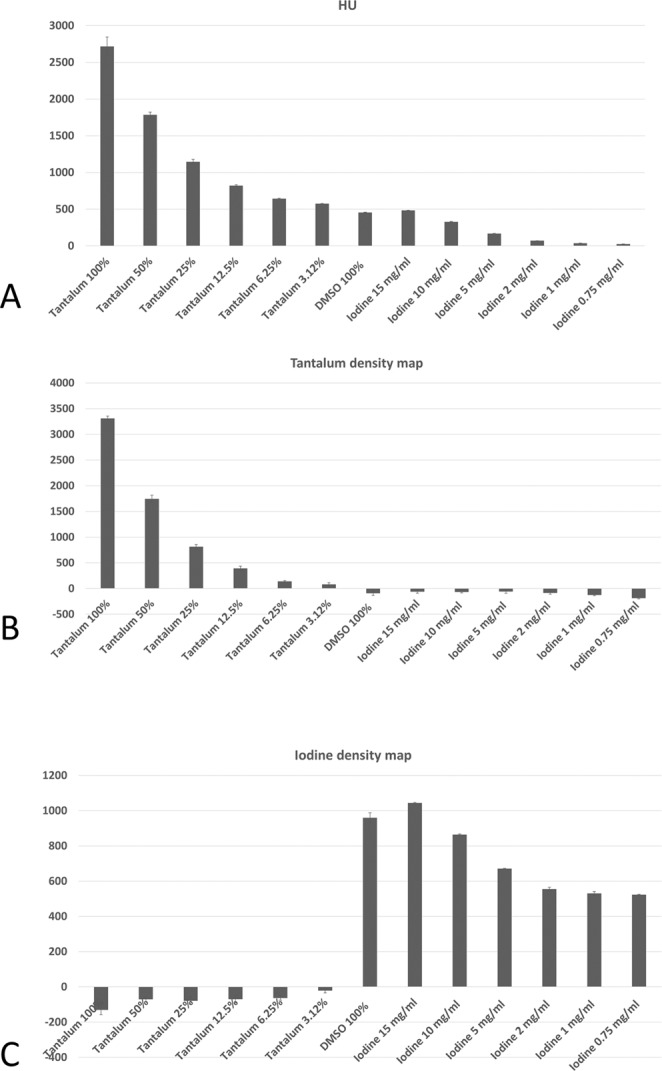

We observe that the TDMs and IDMs provided by SPCCT enable clear differentiation between tantalum and iodine. This is shown in Fig. 5, where Fig. 5A represents the conventional HU values, Fig. 5B the TDM and Fig. 5C the IDM. In the conventional HU-CT, the values of the tubes containing low concentrated tantalum, DMSO or high concentrated iodine are similar and can, therefore, not be differentiated. In the TDM, the values of the tubes correspond to the prepared dilution series; the tubes containing DMSO and iodine have values below 0. In the IDM, the dilution series of iodine can be reproduced and tantalum has negative values. DMSO has similar high values as high concentrated iodine, obviously due to similar physical background.

Figure 5.

Bar plots showing the values of the region-of-interest (ROI) analyses within the tubes in Hounsfield Units (HU), tantalum density maps and iodine density maps.